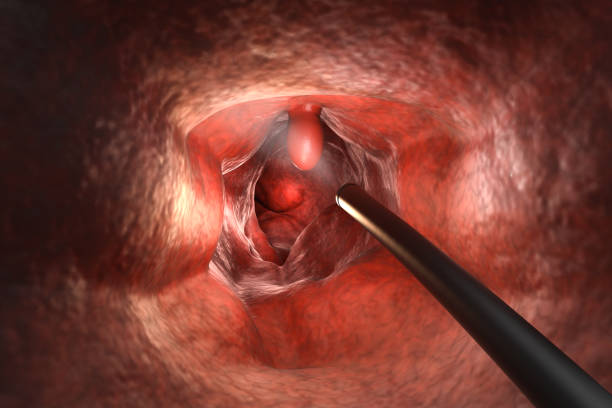

장폐색 치료법

장폐색 치료법은 장폐색의 심각도와 증상의 정도, 환자의 건강상태 등에 따라 다양하게 시행됩니다. 주로 다음과 같은 방법이 사용됩니다.

- 혈관확장술: 도관술, 혈관 스텐트 삽입, 혈관성형술 등을 이용하여 혈관을 확장하거나 협착된 부분을 개선합니다.

- 수술: 치료가 어려운 경우나 합병증이 있는 경우 등에는 수술적 치료가 필요합니다. 부위에 따라 다양한 수술 방법이 있습니다.